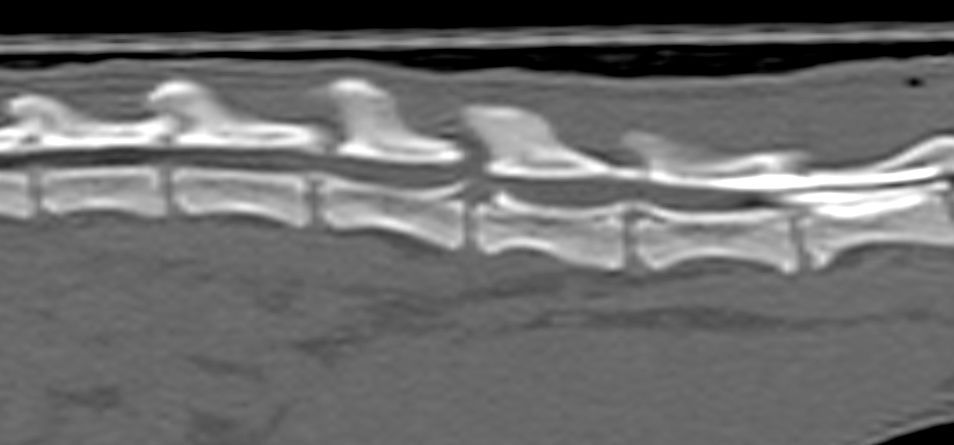

Maladie respiratoire

Les maladies respiratoires des furets sont fréquentes et peuvent se manifester par de la toux, des difficultés respiratoires ou de la fatigue. Il existe de très nombreuses maladies respiratoires et les étiologies les plus fréquentes sont des maladies bactériennes typiques à mycobactéries, pseudomonas luteola, pneumocystis cariini ou des tumeurs.

Le diagnostic se fait par des moyens d'imagerie tel qu'une

radiographie ou un scanner. Dans certains cas, il est nécessaire de faire une

endoscopie afin de réaliser un lavage broncho-alvéolaire pour isoler le germe responsable. Dans certains autres cas, une cause cardiaque doit être recherchée. Le traitement est parfois long et complexe, et nécessite dans tous les cas un diagnostic précis.